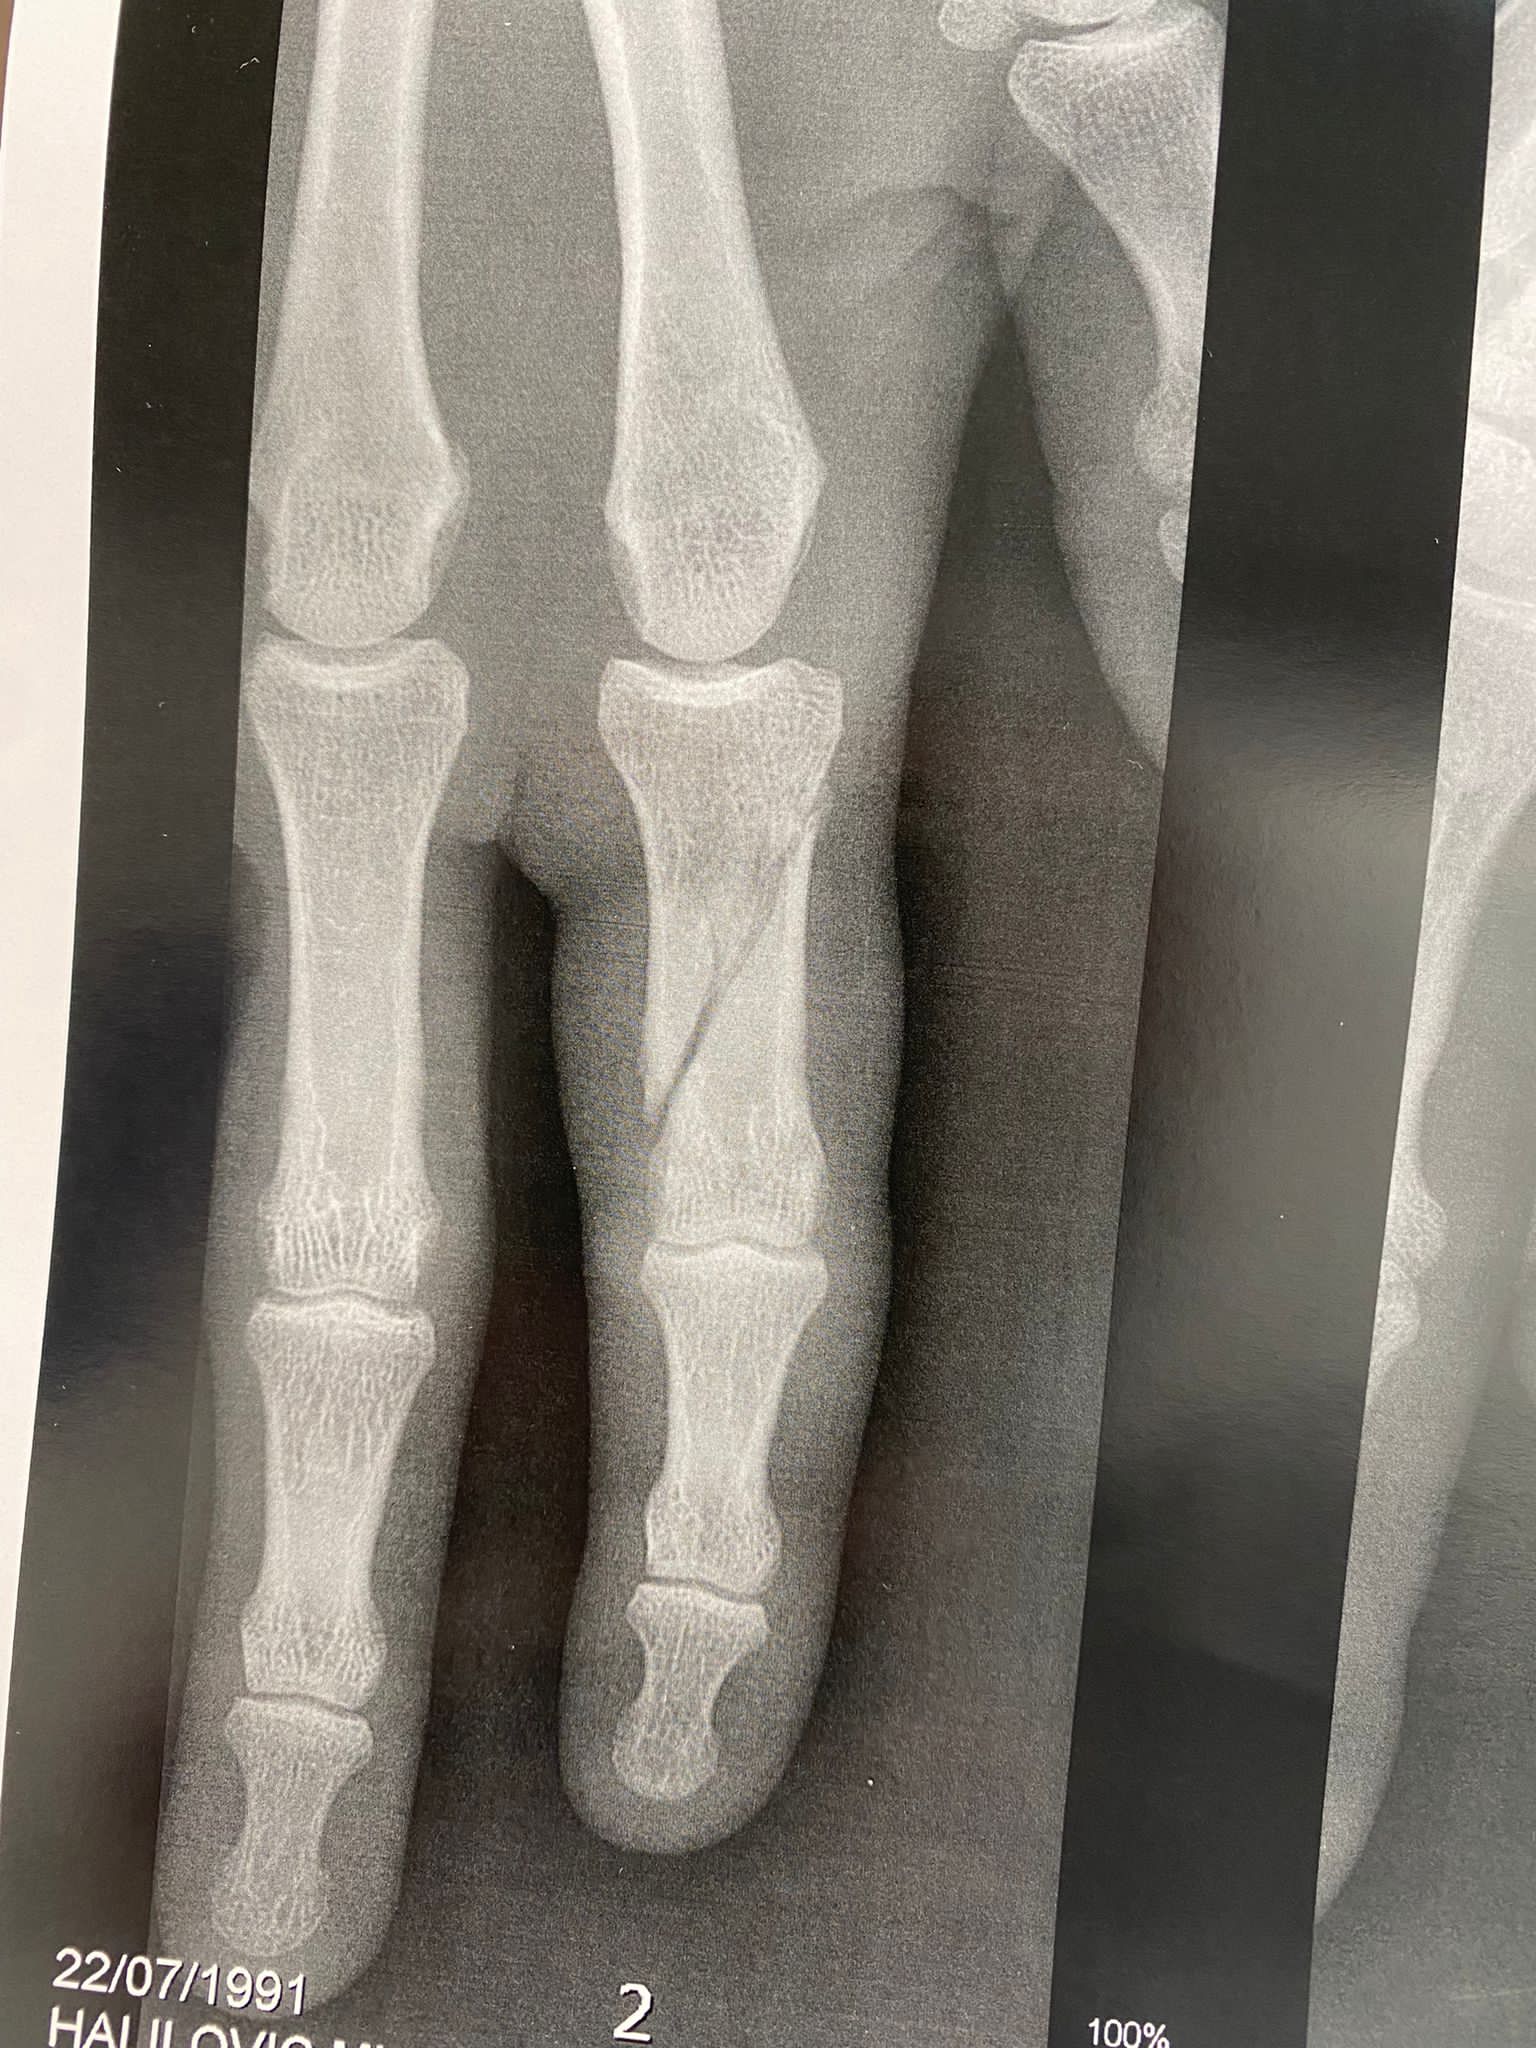

Kapiten košarkaške reprezentacije Bosne i Hercegovine Miralem Halilović doživio je tešku povredu u utakmici francuskog kupa.

Poslije samo četiri minuta igre u kup utakmici između Orelansa i Nanterrea Miralem Halilović je slomio prst. Teška povreda će bh. reprezentativca udaljiti sa parketa prema prvim pognozama najamanje do kraja 2022. godine.

Povreda kapitena Zmajeva je teže prirode, a u foto galeriji koja se nalazi u prilogu možete pogledati trenutni izgled prsta košarkaša Nanterrea.